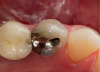

Transilluminating technologies emit light at the base of the tooth at the gingival area and transmit light up through the tooth. At the applied wavelength, enamel starts to absorb fewer photons and water starts to absorb more photons, so lesions appear as dark areas on a monitor.6-8 This visualization can be helpful not only for the clinician to identify and diagnose problematic areas (Figure 1), but it also allows patients to see all aspects of their mouth including their cheek, tongue, and tooth, as well as the areas that have decay, thereby potentially assisting in case acceptance.

Transillumination can be used in interproximal, occlusal, and anterior surfaces.5 In many cases the technology is able to show how expansive the decayed area is on occlusal areas that may only have a minimal pit that would not allow a probe to be used (Figure 2 through Figure 4). Visualizing the interproximal regions of posterior teeth is possible as well although this may require a specialized fiber-optic tip.6